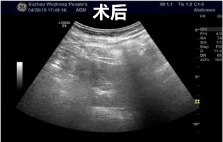

肝囊肿经皮超声引导性介入治疗

2、超声引导下囊肿抽液硬化治疗,肝囊肿、肾囊肿穿刺抽液硬化治疗,盆腔囊肿穿刺抽液硬化治疗,甲状腺、乳腺囊肿穿刺抽液治疗。